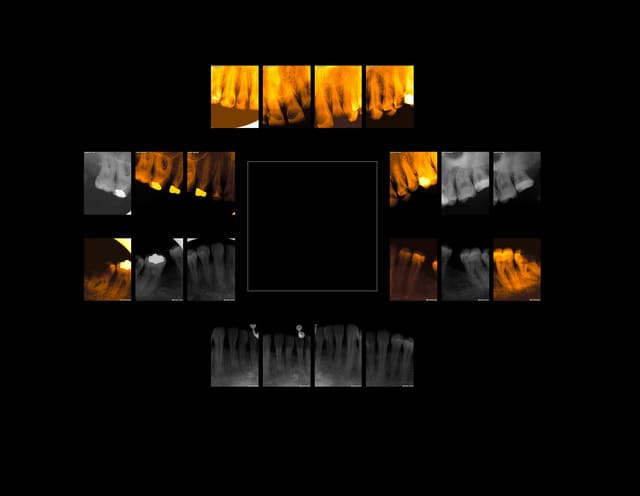

??????? jettes un coup d'oeil au status. C'est plutôt je m'enfoutisme et assistanat de A à Z.

Toutes les couronnes de 15 à 25 et meme au delà sont nazes.